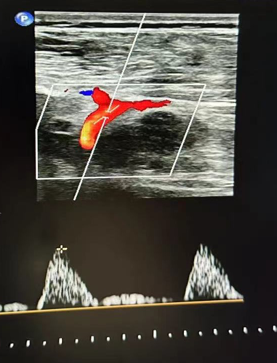

心功能室的李月醫(yī)生在檢查時敏銳捕捉到異常信號:雙側(cè)股總動脈血流頻譜呈特征性“小慢波”——這通常是大血管嚴重狹窄的強烈提示。

然而,蹊蹺之處隨之浮現(xiàn)。醫(yī)生仔細掃查了患者從股動脈直至腹主動脈的整條下肢供血通路,血管結(jié)構(gòu)清晰,未見明顯狹窄或斑塊。

經(jīng)驗豐富的醫(yī)生判斷問題可能潛藏在更近心端的胸主動脈,但該區(qū)域受胸骨遮擋,常規(guī)超聲探查受限。

心功能室王璇主任會診后,結(jié)合異常血流動力學特點,將目標鎖定超聲探查難點——胸骨遮擋的降主動脈胸段!建議行主動脈CT血管成像(CTA)檢查以明確診斷。

CTA結(jié)果印證了王璇主任的判斷:患者降主動脈胸段(距鎖骨下動脈約10厘米處)存在一處少見的先天性局部縮窄,并伴有遠端擴張。這正是導致患者下肢血流灌注不足、多年感覺發(fā)涼的“元兇”——降主動脈縮窄,一種少見的血管發(fā)育畸形!